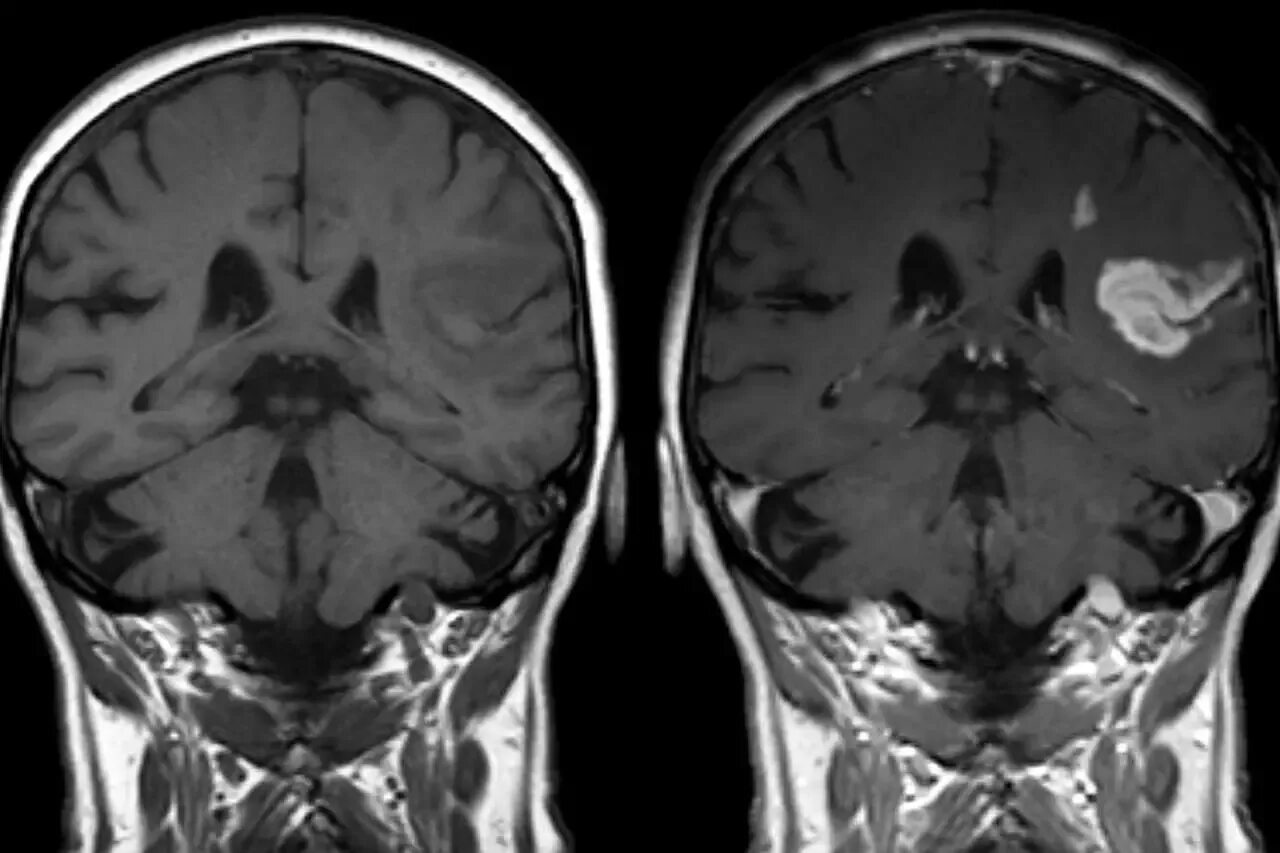

Мрт с контрастом в каких случаях